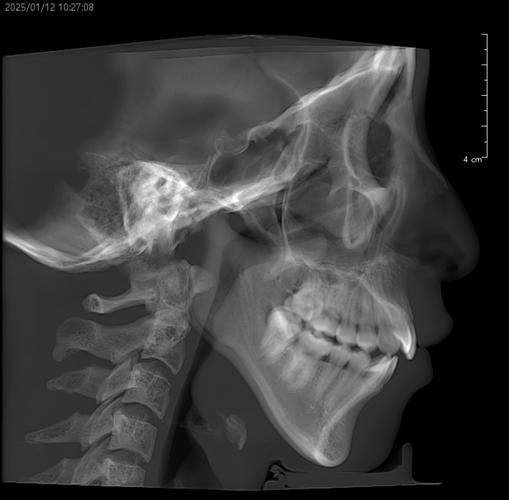

正畸前的全面评估是关键,临床检查需关注张口度(正常约3.5-4.5cm)、有无弹响及疼痛点、下颌运动轨迹是否对称;影像学检查中,MRI可清晰显示关节盘位置、形态及髁突活动度,CBCT能观察骨结构有无破坏(如髁突吸收、关节间隙狭窄);咬合分析需排查早接触、咬合干扰等异常;肌电图可辅助评估咀嚼肌功能状态,根据评估结果,医生需判断关节问题是否为继发于咬合紊乱,正畸能否成为治疗环节之一,或是否需先处理关节问题。